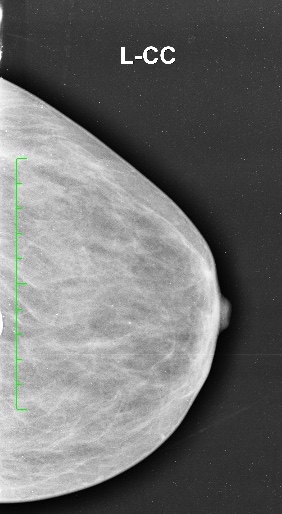

Conventional Xray Mammography It has become widely acceptable method for screening of women after certain age for early detection of malignant and pre malignant conditions of breast.

It is a non invasive technique for quantification of radioactivity after injection of radioactive substance in the body. it has various clinical applications especially oncologic imaging for diagnosis, staging and follow up for treatment response in cancer patients.

Non- oncologic applications are emerging gradually in cases of dementia and other neurological conditions.

Conventional Xray Mammography It has become widely acceptable method for screening of women after certain age for early detection of malignant and pre malignant conditions of breast.